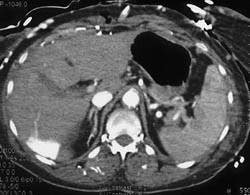

Hot Spot Liver Due to SVC Occlusion